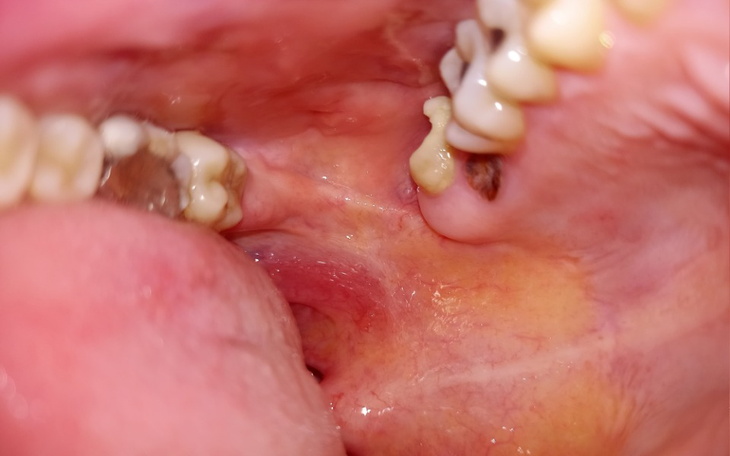

Hej. Jestem Monika. Mam 33 lata a panicznie boję się dentystów. Do tego stopnia że mdleje przed gabinetem. Niestety przez to moje zęby są w tragicznym stanie. Moim marzeniem jest usunięcie zębów tylnich pod narkozą , tak żeby już nie bolało. Nie pamiętam kiedy ostatnio całą noc przespałam. Boli okropnie. Ketanol nie pomaga.